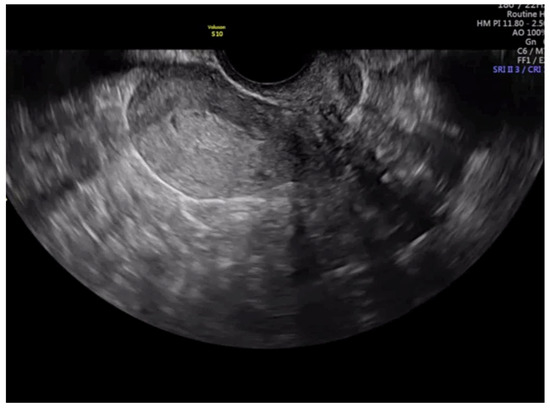

Figure 3. Transvaginal ultrasound showing a case of superficial infiltration in endometrial cancer according to subjective impression.